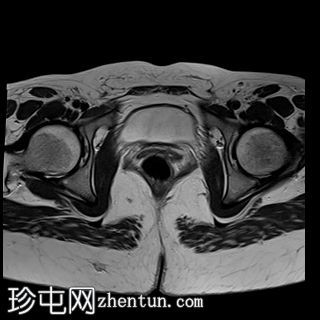

轴位

T2加权像

MRI特征符合剖宫产术后瘢痕子宫内膜异位症,表现为特征性T1高信号伴T1FS持续存在,T2低信号伴内部高信号灶,病灶边缘浸润于腹前壁肌肉内,以及对比增强。

该病灶累及腹白线并浸润腹直肌,主要位于中线左侧,耻骨联合及结节处腹直肌起点上方。

影像学表现符合病灶内出血成分,提示既往剖宫产瘢痕处存在异位子宫内膜组织。

未见明确的腹膜内或皮下软组织侵犯。

双侧卵巢增大,内含多个小卵泡(每侧卵巢10-12个或更多)。